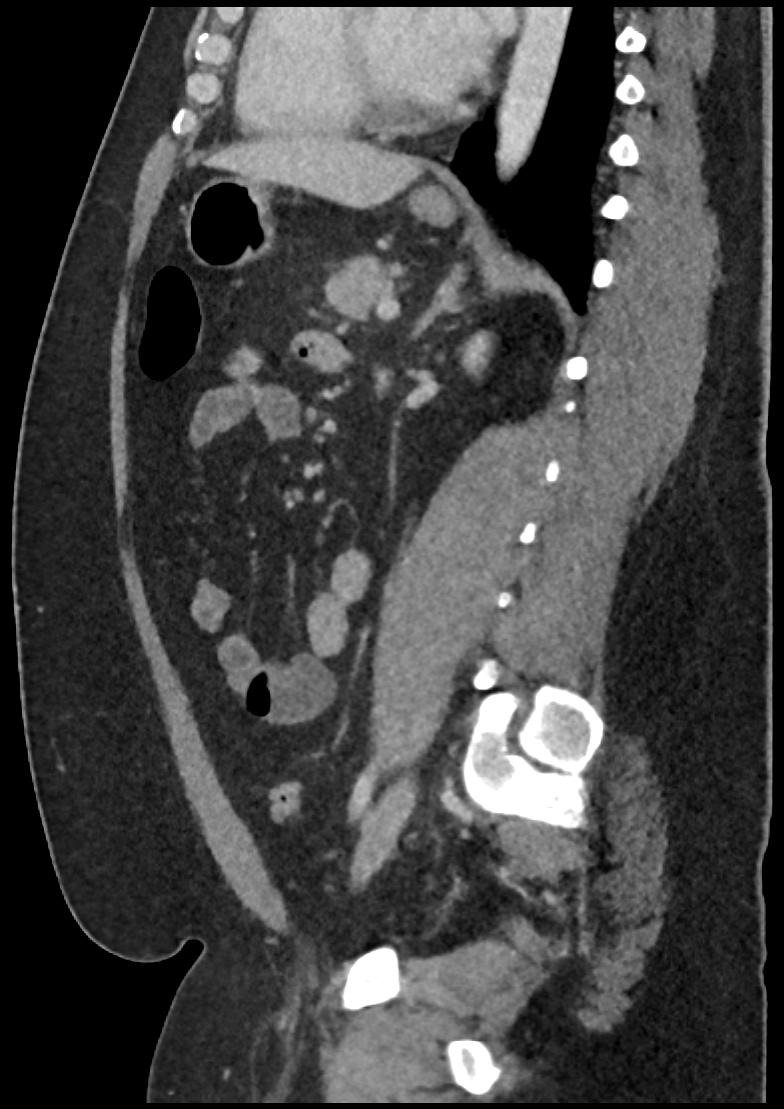

Patient: Padmakumar A. , *1988-04-24, PID: 3000069741773230809

Study Description: CT ABDOMEN

Image Series: Abdomen Sag 3mm [4]